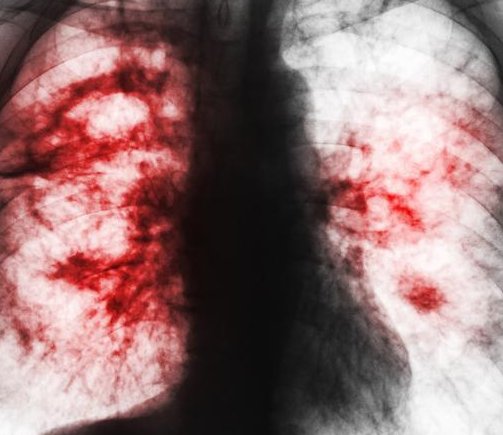

非小细胞肺癌(NSCLC)约占所有肺癌的85%,其影响面大、破坏力强,是肺癌家族中最大的黑恶势力。而在NSCLC患者中,约1/5的患者都为局部晚期(III期)。

非小细胞肺癌(NSCLC)约占所有肺癌的85%,其影响面大、破坏力强,是肺癌家族中最大的黑恶势力。非小细胞肺癌可以进一步细分为肺鳞癌、肺腺癌和肺大细胞癌,其中肺腺癌及肺鳞癌是最常见的类型,分别约占肺癌的40%-50% 及30%-35%。

之所以将III期非小细胞肺癌,称为局部晚期,是指在位置上,肿瘤被限定在肺部原发灶附近;而在疾病进程上,肿瘤已通过淋巴转移逐步浸润,但还没有发生远处转移(如骨、肝、肾上腺、脑等脏器)。III期非小细胞肺癌可以进一步细分为IIIA、IIIB和IIIC期,5年生存率分别对应为36%、26%和13% 。